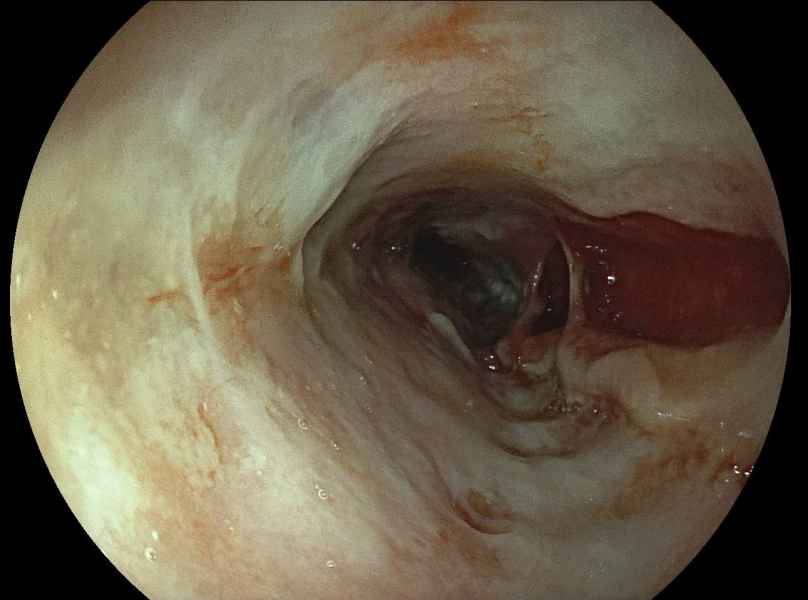

Severe alendronate-induced esophagitis in a young patient